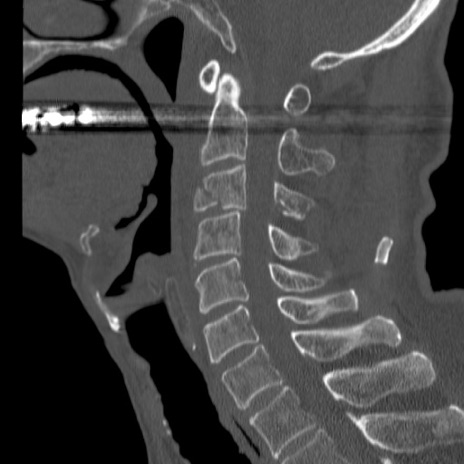

症例46 頚椎CT(矢状断像)

【症例】80歳代男性

【主訴】両側頚部〜上肢のしびれ

【現病歴】昨日、自宅内で転倒、その後より上記症状あり。意識障害なし。

【身体所見】両側上肢のallodynia(熱痛覚過敏)あり。MMTおよびDTRは正確な所見取れず。両上肢の挙上はなんとか可能。

異常所見と診断は?